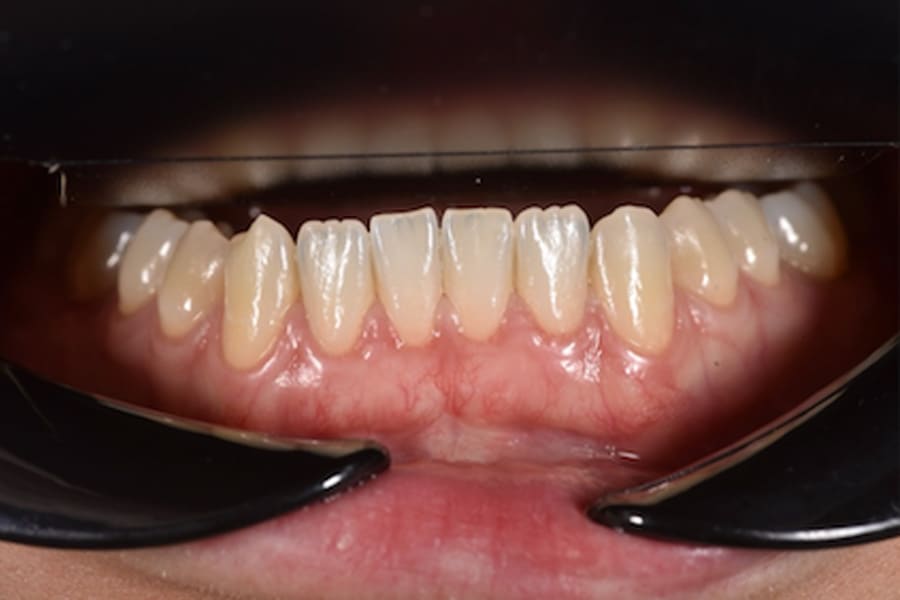

A 31-year-old female patient presented with the following intraoral conditions: an anterior open bite, bimaxillary crowding, negative crown torque, early “black triangles,” and a thin phenotype/biotype with early recessions. Her extraoral situation included a gummy smile with high-lip mobility, asymmetric arch forms and posterior corridors, and incompetent lip closure (Figure 2 through Figure 4). Collectively, these factors increase esthetic and periodontal risk and favor posterior intrusion over anterior intrusion.4-8,12-16

In thin phenotypes with early recessions, minimally invasive tunneling with CTG (with enamel matrix proteins on exposed roots when indicated) can increase soft-tissue thickness and support long-term stability after orthodontic tooth movement.12-16 (Figure 14 through Figure 17)